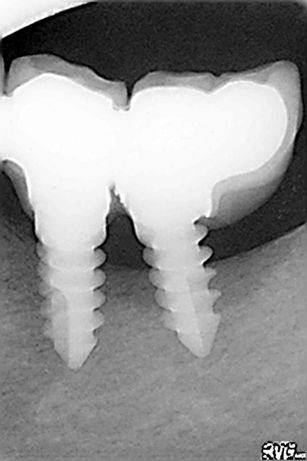

j’ai fait posé 3 implants de marque (implant Monobloc Biomédical trinon) origine Allemagne? chez le dentiste qui travaille avec endurance Implant, j’ai perdu un premier implant 2 mois après la pose, j’ai fait une péri-implantite dentaire, avec poche de pus (grave), j’ai joint par téléphone le cabine dentaire près de Barcelone, aucun problème au dire du dentiste d’après ma radio ? Pourtant le médecin stomatologue ma recommande d’urgence de revoir le dentiste pour faire coupé l’implant qui été sortie de l’os? risque d’infection de la mâchoire, car mal posé d’après lui. je vient encore d’avoir de nouveau des problèmes sur un 2eme implants infection a la base, je vient de faire une radio l’implant est sortie de l’os?

résultat sur 3 implants dentaires il m’en reste un.

mes radios seront bientôt sur internet pour comprendre.